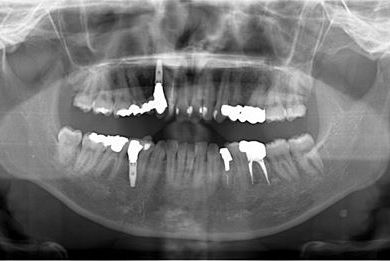

| 性別/年齢 | 女性 / 29歳 | ||||||||||||||||||||||||||||||||

| 主訴 | 以前治療中のままだった部位の歯の根に膿が溜まって、痛みと腫れが出た。応急処置で切開して膿は取ってもらったが、根の治療がまだなので、お願いしたい。 | ||||||||||||||||||||||||||||||||

| 治療方針 | 抜歯と同時にインプラント埋入を行い、治療期間を短縮する。 | ||||||||||||||||||||||||||||||||

| 治療内容 | インプラント2本(抜歯即日スピードインプラント)、ハイブリッドセラミッククラウン3本 | ||||||||||||||||||||||||||||||||